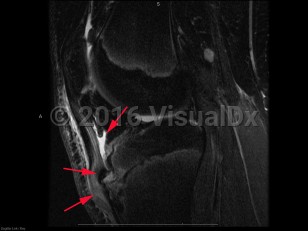

Causes / typical injury mechanism: Osgood-Schlatter disease (OS), also known as juvenile osteochondrosis of the tibial tubercle, is a disorder involving inflammation, pain, and swelling of the tibial tuberosity. It is most common in young adolescents, particularly those regularly involved in athletics. OS typically occurs soon after a growth spurt. Symptoms last for 12-18 months, often resolving spontaneously with the closure of the physeal plate of the tibia, although there is a small subset of patients who experience pain after skeletal maturation.

Pathophysiology: The underlying pathophysiology of OS is poorly understood. Its association with sports participation has led to the hypothesis that it is related to repeated small injuries to the developing knee associated with traction from the patellar tendon.